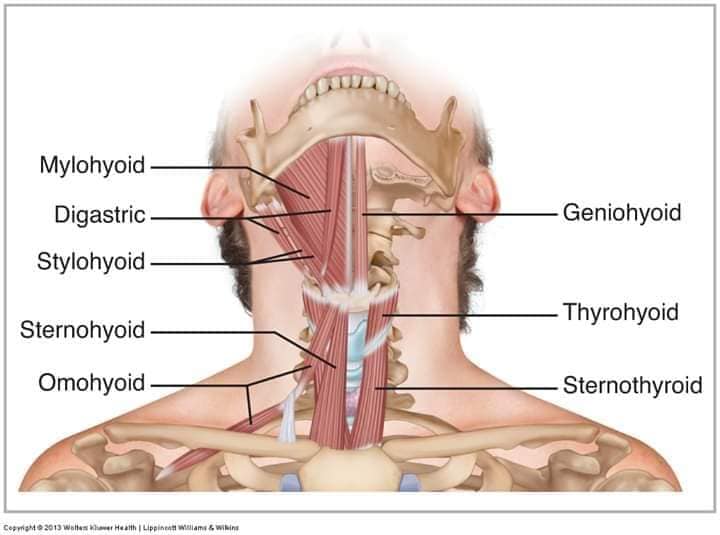

Шийні м'язи мають важливе значення для підтримки голови і забезпечення її рухів.

М'язи передньої групи

М'язи, що згинають шию: М'язи, що згинають голову (м'язи передньої групи): виконують рухи, які дозволяють опускати і піднімати голову.

М'язи бічної групи

М'язи, що повертають голову: Стерноклейдомастоїдний м'яз: один з найважливіших м'язів, який дозволяє здійснювати повороти і нахили голови. Він походить від грудини та ключиці і прикріплюється до соскоподібного відростка скроневої кістки.